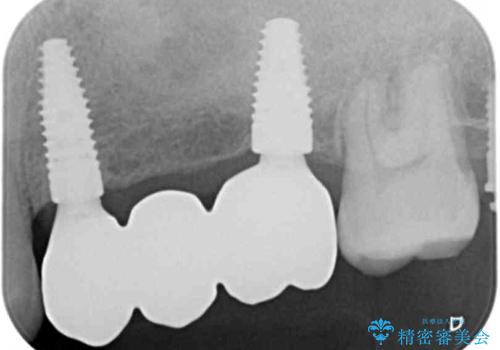

・重度虫歯による残根状態・欠損歯→インプラント補綴

・対合歯の欠損による歯の挺出→マイクロインプラントを用いた小矯正を行うことで咬合平面を是正

特定の歯に過大な力がかかることなく安定した咬合関係を構築できるよう治療計画を立案します。